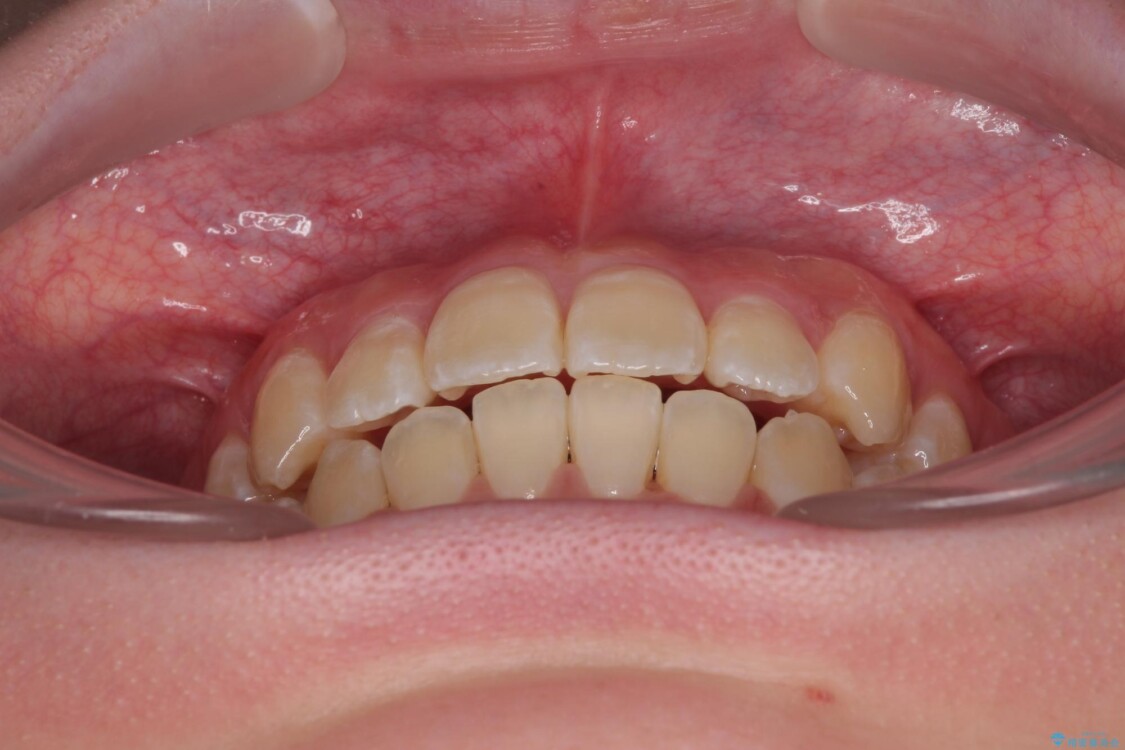

「前歯のデコボコ(叢生)をきれいに整えたい」とのことでご来院されました。

治療前

• 【モニター】前歯のデコボコをスッキリ解消!目立ちにくいワイヤー矯正でスピーディに治療完了 治療前画像